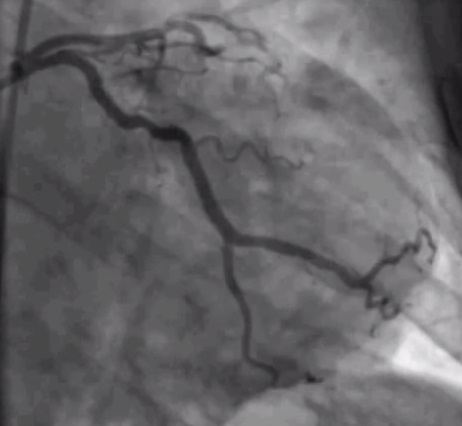

A coronary angiogram is a procedure that allow us to see the arteries that supply blood to the heart very clearly. These arteries, called coronary arteries, can become narrowed with plaque, leading to a reduced blood supply to the heart (called ischaemia) and potentially a heart attack.

- Now the doctor will pass a long thin tube (catheters) up towards the heart, and through them they will inject some dye (contrast), and using foot pedals, they will take X-rays so they can see the arteries around your heart.

- The doctor will swap the catheter (or sometimes, use the same one) to a different shaped one to take pictures of the artery on the other side of your heart.

- And that’s it! All the pictures are taken and your doctor will review them. They will be able to tell you very quickly if there is a problem that needs fixing. Occasionally, they will need to review your images on a workstation outside to get a better look.